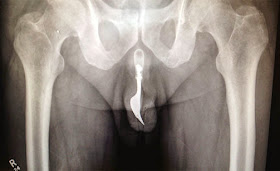

”Uutisessa kerrotaan, että noin 70-vuotiaan australialaismiehen peniksen sisältä jouduttiin kaivamaan ulos noin kymmenen senttimetrin pituinen haarukka.

Haarukka munissa

Muun muassa Huffington Post, NY Daily News sekä Daily Mail -lehdet kertovat, että haarukka oli päätynyt penikseen miehen erikoisesta seksileikistä, jossa hän oli yrittänyt tyydyttää itseään työntämällä vierasta esinettä virtsarakkoonsa. Mies saapui sairaalaan kovista kivuista kärsivänä ja joutui myöntämään tekonsa.

Huffington Post kertoo, että haarukka saatiin onnistuneesti poistettua, mutta lääkäreiden mukaan miehen harrastama leikki olisi voinut olla hengenvaarallinen.

Miestä hoitaneet lääkärit halusivat tuoda esimerkin julkisuuteen herättääkseen lääketieteen alalla keskustelua erikoisten ja kummallisten tapausten kohtaamisesta, Daily Mail kirjoittaa. Lääkärit kommentoivat, että potilaan motiiveja teolleen on vaikea käsittää.

Miesten virtsarakoista löytyy äärimmäisen harvoin vieraita esineitä, mutta Daily Mailin mukaan ihmiskehoista on poistettu muun muassa kyniä, puhelinjohtoa, pattereita, hammasharjoja ja muovihansikkaita.”